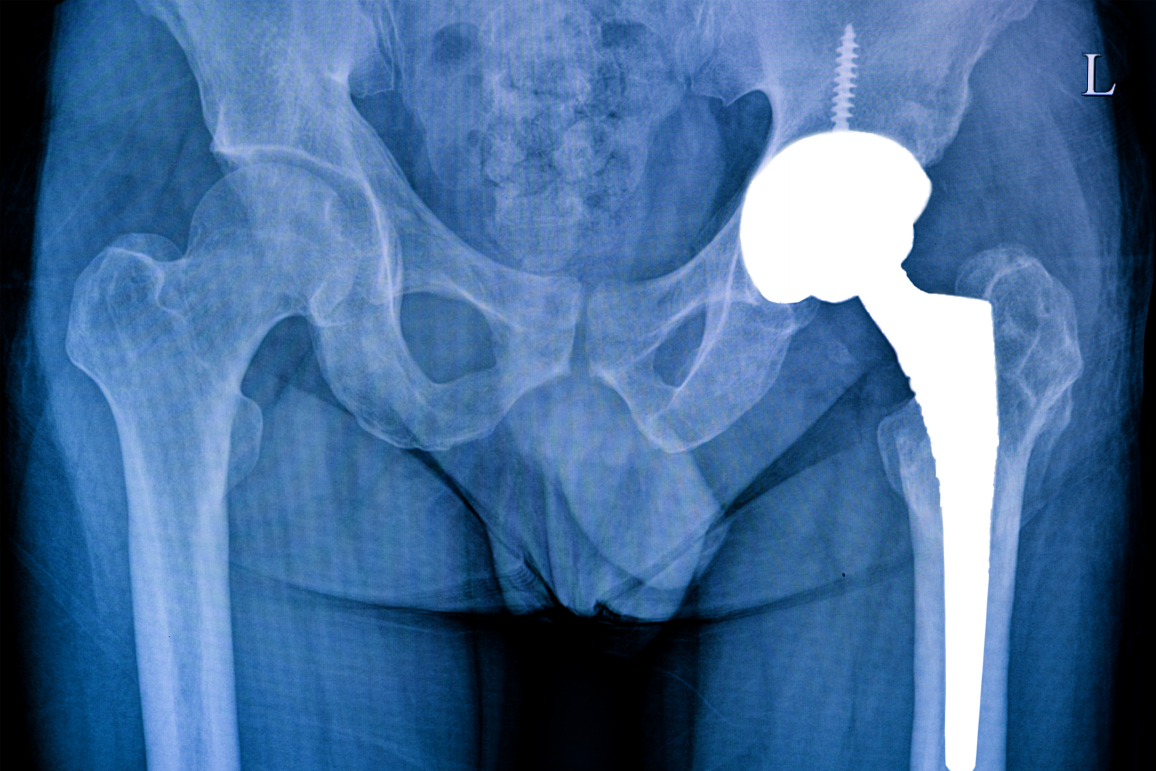

Хирургическое лечение

В некоторых случаях необходимо хирургическое вмешательство, особенно при множественных, открытых переломах или если консервативное лечение не дает нужных результатов. В таком случае применяется остеосинтез, который включает использование металлических пластин, винтов или штифтов для стабилизации отломков.